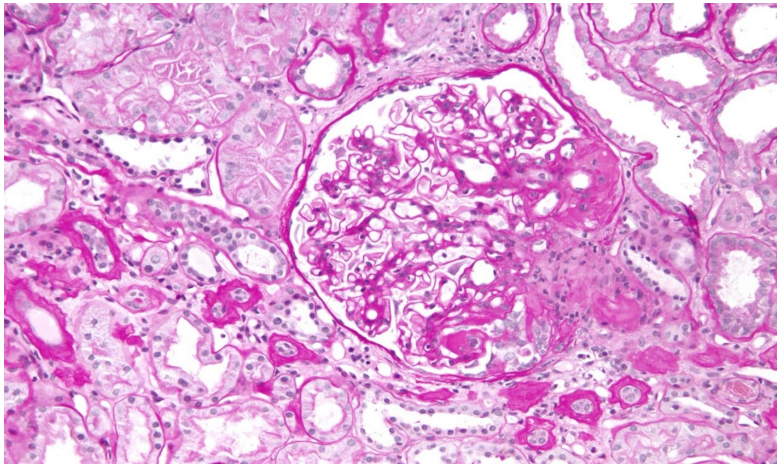

Fig 4: kidney with focal segmental glomerulonephritis

• Kidney Biopsy: Confirmed focal segmental glomerulonephritis (lupus nephritis Class III-ISN/RPS 2004) and hypertensive vasculopathy.